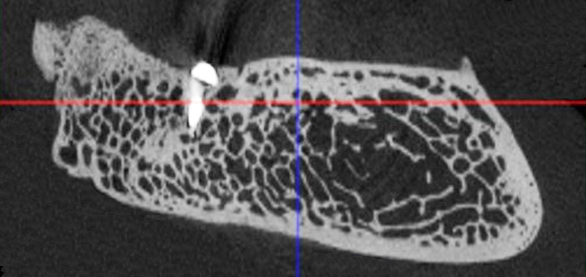

Рис. 1. Поперечный срез микротомографии локтевого отростка овцы

Учитывая выше перечисленные недостатки, поиск новых областей и способов хирургического доступа для создания экспериментальной модели исследования остеопластических материалов является актуальным. Нас заинтересовало использование в качестве экспериментальной живой модели область локтевого отростка передних конечностей овцы. В доступной литературе нами не встречено упоминаний об использовании локтевых отростков овец с целью формирования костных дефектов для оценки регенераторного потенциала остеопластических материалов. Вероятно, это обусловлено боязнью риска травматизма локтевого отростка в ходе формировании дефекта при использовании классического хирургического инструментария – сверл и фрез большого диаметра. Между тем очевиден ряд преимуществ данной области – схожее анатомическое строение и архитектоника с альвеолярной частью челюстей человека. Локтевой отросток имеет наружный кортикальный слой и внутренний, представленный губчатым веществом с костномозговыми пространствами небольшого размера (рис. 1, 2).

Рис. 2. Поперечный срез альвеолярной кости верхней челюсти человека в проекции отсутствующего премоляра (А) и альвеолярная кость нижней челюсти человека в проекции отсутствующего моляра (Б). 3D-КЛКТ